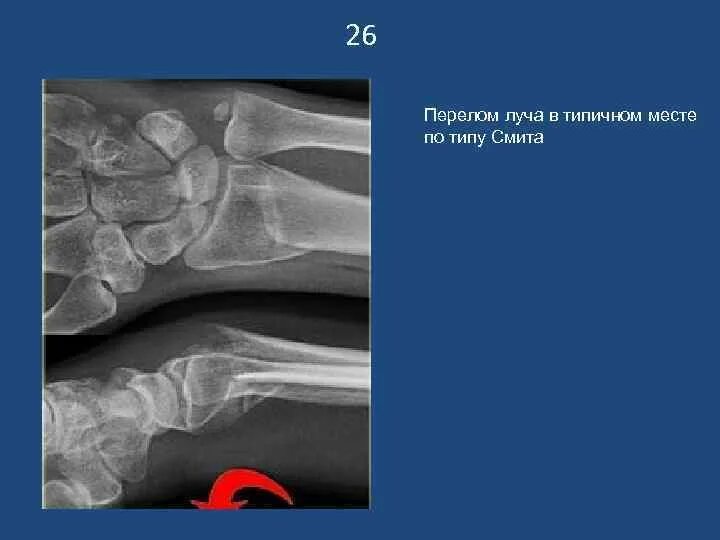

Перелом смита